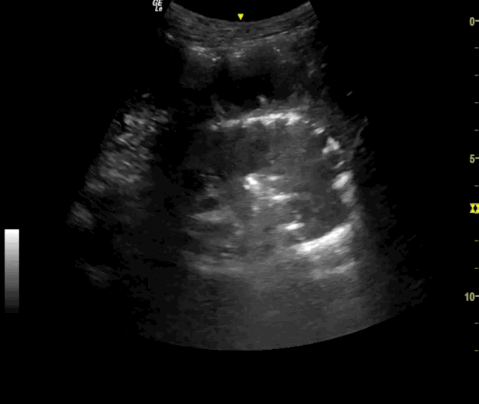

Typisches „circle sign" bei pneumatosis intestinalis; Try out pmc labs and tell us what you think. 28/06/2010 · my ncbi sign in to ncbi sign out. Im akuten stadium plötzlich beginnender, starker und seitenbetonter unterleibsschmerz mit … Us national library of medicine national institutes of health.

Typisches „circle sign" bei pneumatosis intestinalis;